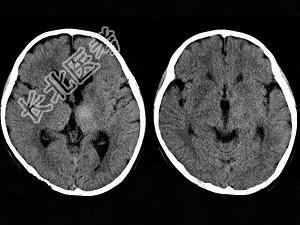

- 单项选择题女,12岁, 进行性肢体震颤1年余,多次出现发音困难, CT、MRI检查如图所示,最可能的诊断为  (    )

A、肝豆状核变性

B、脑萎缩

C、双侧基底节区多发梗死

D、脱髓鞘改变

E、脑积水